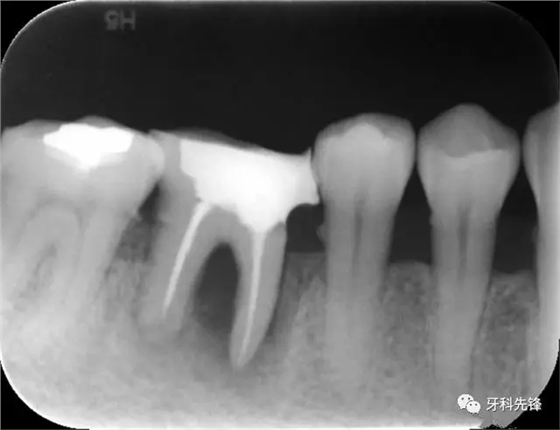

X 示:15 根管透射,根尖有陰影

14根管阻射,恰填,無異常

46 根管阻射,恰填,根分叉骨密度降低,近中根尖陰影較大

圖1術(shù)前X光片

圖8治療術(shù)后X光片

圖1814 15 三個月后X光片(根尖陰影減小)